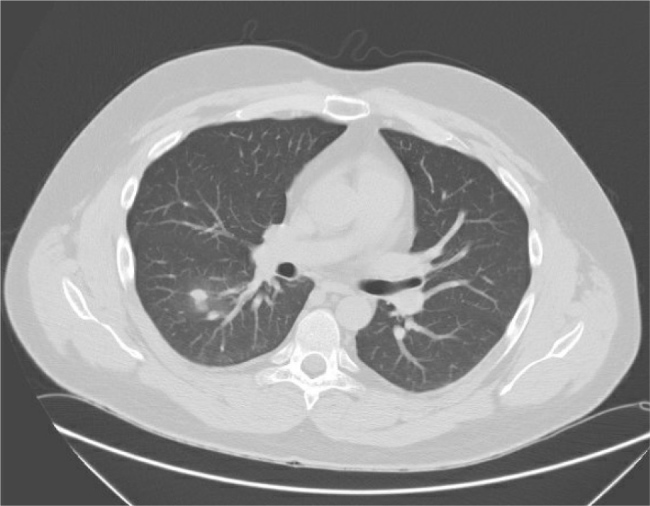

Case description: We report the case of a 29-year-old male who presented with new-onset diabetes mellitus, resistant hypertension and significant weight gain. Physical examination revealed features consistent with Cushing's syndrome. Biochemical evaluation confirmed ACTH-dependent hypercortisolism with an elevated plasma ACTH level, and a lack of suppression on high-dose dexamethasone testing; imaging identified a suspicious pulmonary nodule. Bronchoscopic biopsy revealed no malignancy, however cultures grew Rhodococcus species. The patient denied any respiratory symptoms or environmental exposure. Initial antibiotic therapy with ciprofloxacin and rifampin was started. Follow-up imaging showed rapid enlargement of the pulmonary mass, prompting surgical resection. Histopathology revealed malakoplakia, and repeat cultures again yielded Rhodococcus spp. Antibiotics were adjusted to azithromycin and rifampin, and the patient was started on ketoconazole to manage hypercortisolism.